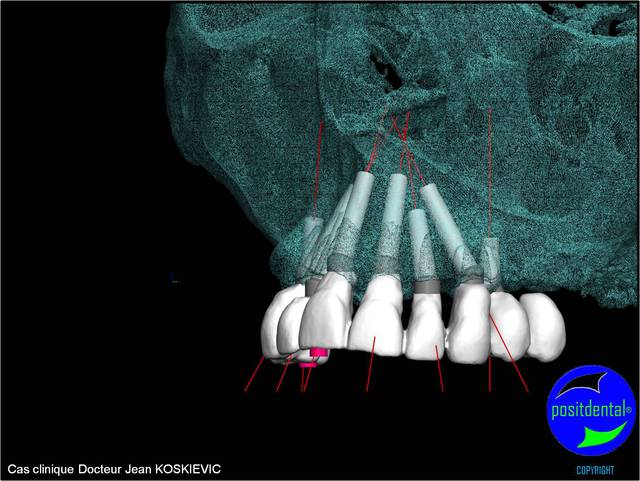

et la projet 10 implants maxillaire sup

Béotien, le guide chirurgical est dispositif médical sur mesure, c’est la raison pour la quelle j’ai choisi de le concevoir et réalisé en acier chirurgical, il peut ainsi être stérilisé pour correspondre aux recommandations de la HAS (haute autorité de santé), son design et étudié pour facilité l’irrigation externe, les outils connexe soit standard soit développés spécifiquement par Positdental ont le marquage CE et ma qualité de prothésiste dentaire m’autorise à remplir le certificat de conformité répondant aux exigences relative à directive européenne n° 93/42 CEE. Pour la deuxième question une formation clinique et théorique par des praticiens sous l’égide du Docteur Jean KOSKIEVIC et technique ainsi que des cas cliniques accompagnés se met en place. En effet l’implantation bi maxillaire est complexe et demande beaucoup d’attention.